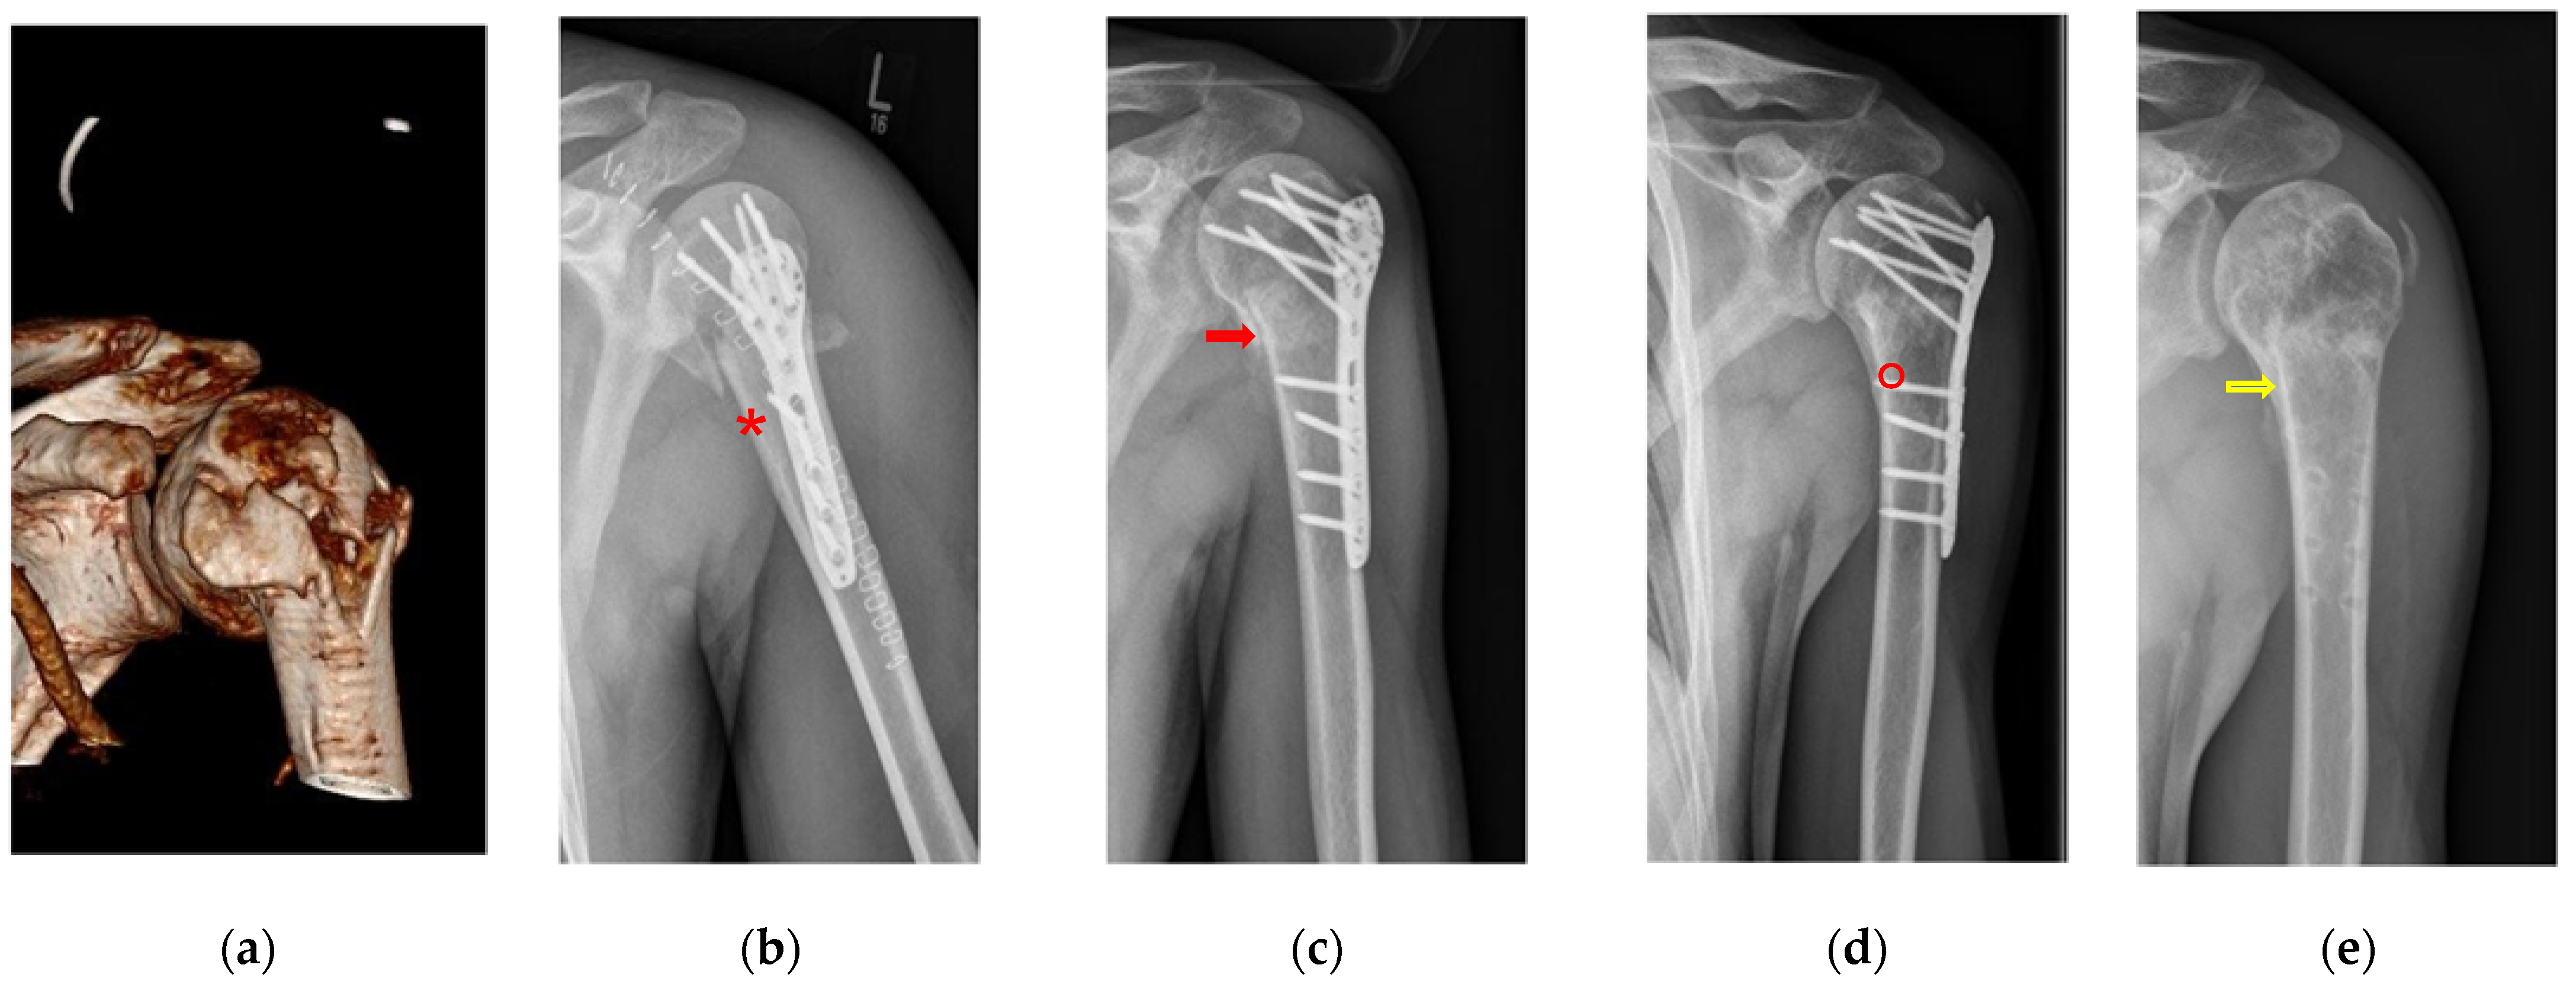

Figure 2.

Fracture morphology grading system determined the grade based on the criteria of the bone healing process. (a) Morphology of a simple articular fracture prior to surgery (AO classification 11C3.1x). (b) Borders of fracture are sharply edged with a wide fracture gap and a loss of density (*). (c) Dimly visible edges of the fracture border with a slightly increasing density in the fracture gap (red arrow). (d) Advanced bone healing process shows increased bone density in the fracture gap without fracture borders (°). (e) Optimal osseus healing process of the fracture borders with increased local bone density in the region of the fracture gap (yellow arrow).

The fractures were divided into four areas for evaluation (Table S1). Initially, the fracture edge was sharply defined in the initial days post-trauma (grade 5). Subsequently, due to fracture displacement and the bone remodeling process, the bone density within the fracture gap diminished, resulting in a visible, pronounced fracture gap (grade 5). Following the acute phase, the fracture edge lost its sharpness within three to four weeks. Radiographs displayed the loss of sharp edges (grade 4) and indistinct bone gaps (grade 4). Meanwhile, compaction within the fracture gap and faintly visible fracture edges indicated a state preceding optimal healing (grade 2). If optimal osseous fracture healing (restitutio ad integrum) was achieved, the highest grade (grade 1) was assigned. It is noteworthy that four to six months are typically required for optimal bone healing [34]. Variations in the articular surface and differences in the osteosynthesis material were also considered (Table S1).